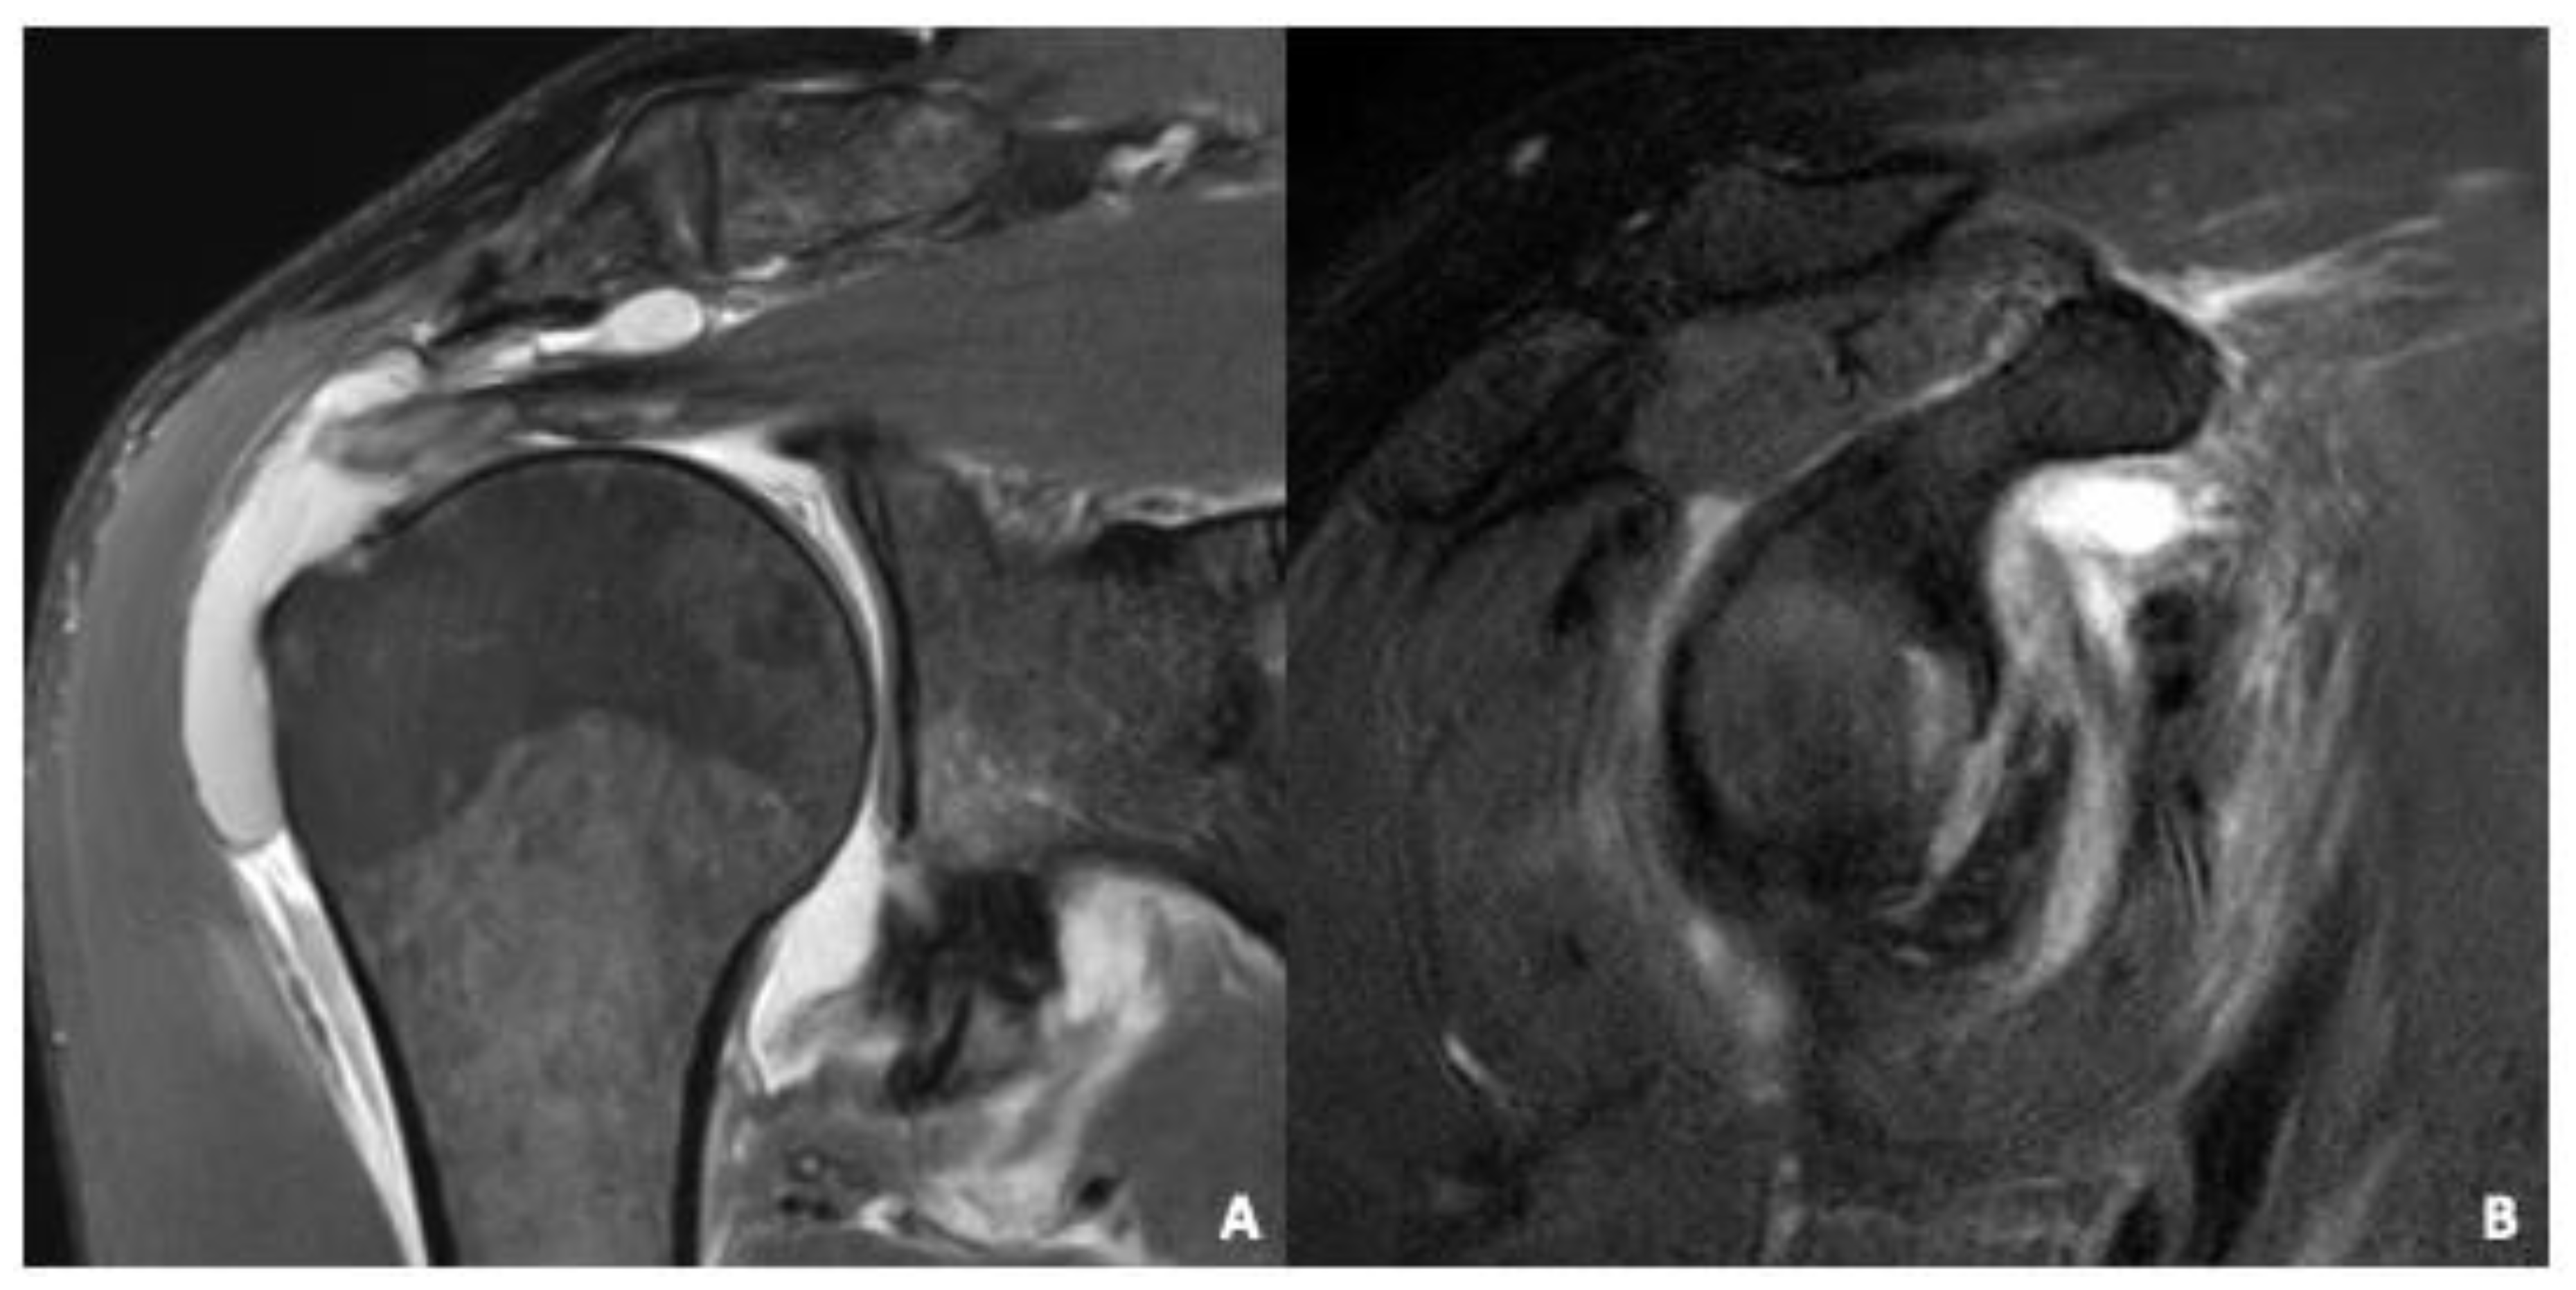

| Rotator cuff tendons | Tendinopathy including: subacromial impingement, rotator cuff tendinitis/tendinosis, calcific tendonitis. | No pathology: 10 (30%) Tendinopathy: 16 (48%) Partial or complete tear: 20 (61%) |

| Rotator cuff muscles | Fatty infiltration assessed according to Goutallier et al. [27] | No pathology: 24 (73%) Fatty infiltration: 0 (0%) Acute injury: 9 (27%) |

| Labrum | Assessment for defects of the labrum e.g., antero- inferior after dislocation, anatomical variations of the labrum according to Kanatli et al. [29] | Normal Labrum: 1 (3%) Anatomical normal variant: 0 (3%) Lesion: 32 (97%) |